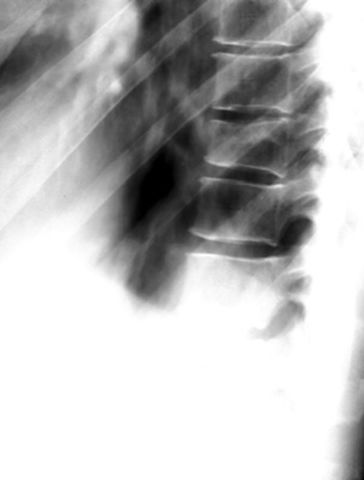

正常腰椎

疼痛科怎么理疗疼痛科医生、康复理疗科医生、针刀针灸医生应掌握的常见骨科疾病X光片_https://www.jmylbn.com_新闻资讯_第57张

L5腰椎骨折

疼痛科怎么理疗疼痛科医生、康复理疗科医生、针刀针灸医生应掌握的常见骨科疾病X光片_https://www.jmylbn.com_新闻资讯_第58张